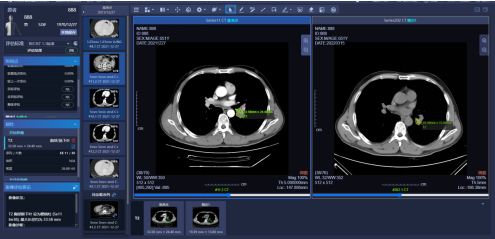

围绕肿瘤新药临床试验的影像评估的规范要求,放射科与麻省总院蔡文立教授合作,引入肿瘤影像智能评估系统,借助人工智能技术,规范肿瘤影像规范评估和项目管理。

图X:智能化肿瘤影像评估系统